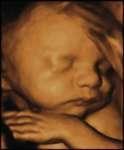

據新華社訊息 多名英國衛生部門官員說,一項旨在規避新生兒先天疾病風險的試管授精新技術可能最先在英國投入使用。

三父母從基因角度看,以這一新技術孕育的試管嬰兒將有一位父親和兩位母親,因而引發“造人”爭議。

這一試管授精新技術的關鍵在於移除女性卵子線粒體中的有缺陷基因。

這種細胞器攜帶自身的基因材料,稱為線粒體基因組。在一些情況下,線粒體基因組可能發生突變,產生缺陷,從而導致新生兒罹患先天疾病。英國每6500名兒童中有一人生來患有“線粒體基因病”,引發肌肉虛弱、失明和心臟病。

線粒體只經過母嬰遺傳。因此,研究人員希望藉助全新試管授精技術去除母親卵子中有缺陷的線粒體,從而在更大程度上確保新生兒健康。